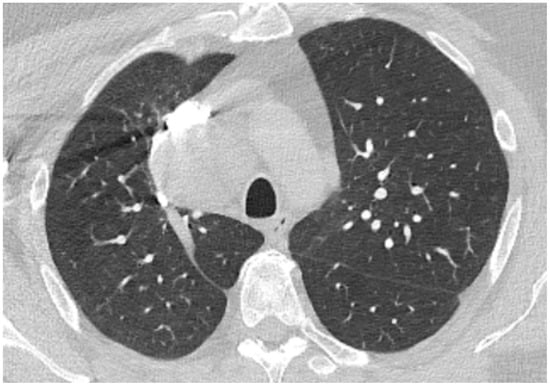

Considering possible sepsis of unknown origin, antibiotics were initiated with ceftriaxone. A sputum culture was positive for Klebsiella pneumoniae spp pneumoniae, and ceftriaxone was continued according to the antibiogram. Blood cultures taken consecutively were negative. During day 3, a thorax CT scan was performed, which showed fine areas of ground glass arranged peripherally and classified as minimal lung damage (Figure 5) and small bilateral areas of pleurisy with a maximum thickness of 10 mm in the right costo-phrenic recess. Methylprednisolone was given, with progressive decreasing of the dose over time. Standard medication for heart failure with a reduced ejection fraction was given [14]. The serum level of interleukin-6 was 2.32 pg/mL, which was considered to be normal [15]. The evolution was favorable: cardiac enzymes, inflammatory markers and procalcitonin continued to decrease and eventually were normalized. Kidney function was preserved. The muscle pain in the upper limbs subsided, with full recovery of functionality. Patient tested negative for SARS-CoV-2 infection on day 14 (RT-PCR).

Figure 5. Native chest computer-tomography in the context of confirmed SARS-CoV-2 infection: fine areas of ground glass arranged peripherally classified as minimal lung damage.